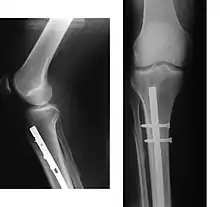

La fracture du tibia est généralement traitée par ostéosynthèse, c'est-à-dire par le replacement éventuel et le maintien de l'os en position anatomique, le plus souvent avec un clou centro-médullaire ou bien à l'aide de plaques et de vis. Dans la fracture double de la jambe, le péroné n'est traité par ostéosynthèse que s'il est atteint à proximité d'une articulation (genou ou cheville). L'ostéosynthèse accélère la reprise de l'appui, qui ne se fait qu'après contrôle radiographique de la consolidation.